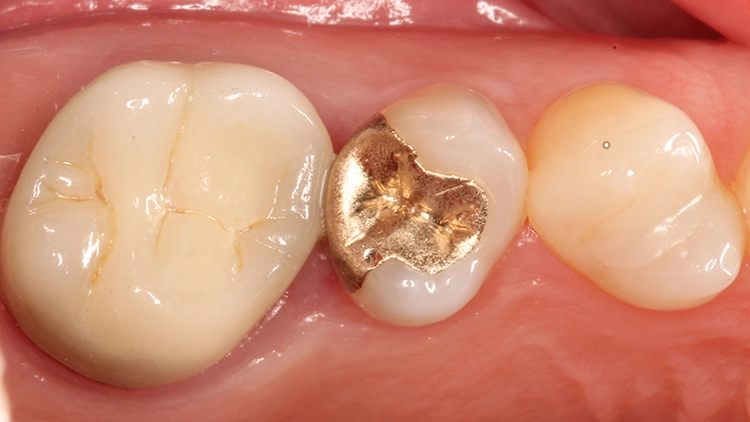

Zur Illustration der Indikation „Inlayaustausch“ dienen die folgenden 3 Fallbeispiele: Die beiden ersten zeigen die Versorgung des Zahnes 45, wobei es im 1. Fall um den Ersatz eines Goldinlays und im 2. Fall eines Keramikinlays geht. Beide Kavitäten wurden mit der neuen Universalfarbe Venus Diamond ONE (Kulzer, Hanau) versorgt.

Fall 1: Austausch eines Goldinlays an Zahn 45

Da aufgrund der Randdefekte eine Austauschindikation bestand, wurden das Inlay sowie minimale Restkaries entfernt und die Ränder nachpräpariert. Bei einer direkten Komposit-Neuversorgung können im Gegensatz zu einer Neuversorgung mit einem Keramikinlay spitz auslaufende Ränder in Form des alten Federrandes belassen werden, da das Restaurationsmaterial diese Bereiche ausfließen und somit randdicht versorgen kann.

Die Patientin bat damals um einen Austausch des Goldinlays, da ihr keine Möglichkeiten einer Nacharbeitung am Inlayrand angeboten werden konnten. Die Inlayversorgung zeigte sich sehr weit in den Approximalraum ausgedehnt (Abb. 11 und 12), was nach Aussage der Patientin an der damaligen Indikation eines Lückenschlusses zwischen den Zähnen 25 und 26 lag.